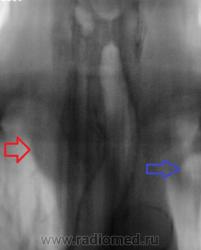

Синяя стрелка, как понимаю "кругляк", который смущает Валентина Львовича? К сожалению край изображения, тяжело что-то понять. Вероятнее всего это 1 ребро.

Зато Красная стрелка - явно зоб